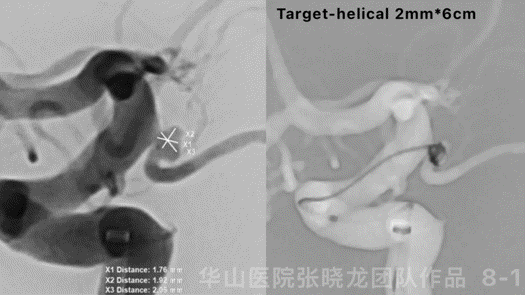

Figure 9. Measurements: An size 2.6*2.1mm, neck 2.1mm, proximal parent artery diameter 4.05mm, distal parent artery diameter 3.95mm. XT-27 was placed into the left ACA, a spiral-curved Echelon-10 was placed into the sac. Deployed a Neuroform EZ 4*15mm. Then two coils (Target-360 2mm*3cm/1.5mm*3cm) was inserted.